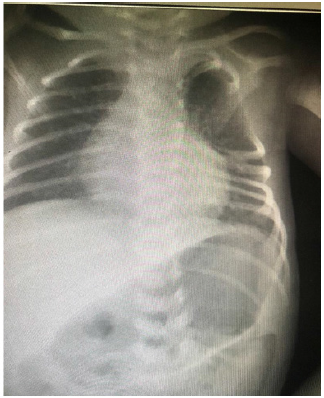

- Chest x-ray show absent 2nd ,3rd 4th left thoracic ribs

- CT Chest show absent left upper 3rd and 4th right ribs

- Fused posterior part of left 5th and 6th ribs, butterfly vertebra.

- Fused left posterior nural of thoracic 3rd and 4th and thoracic 5th

- To roll out vactral anomalies (Figure 1 & 2)